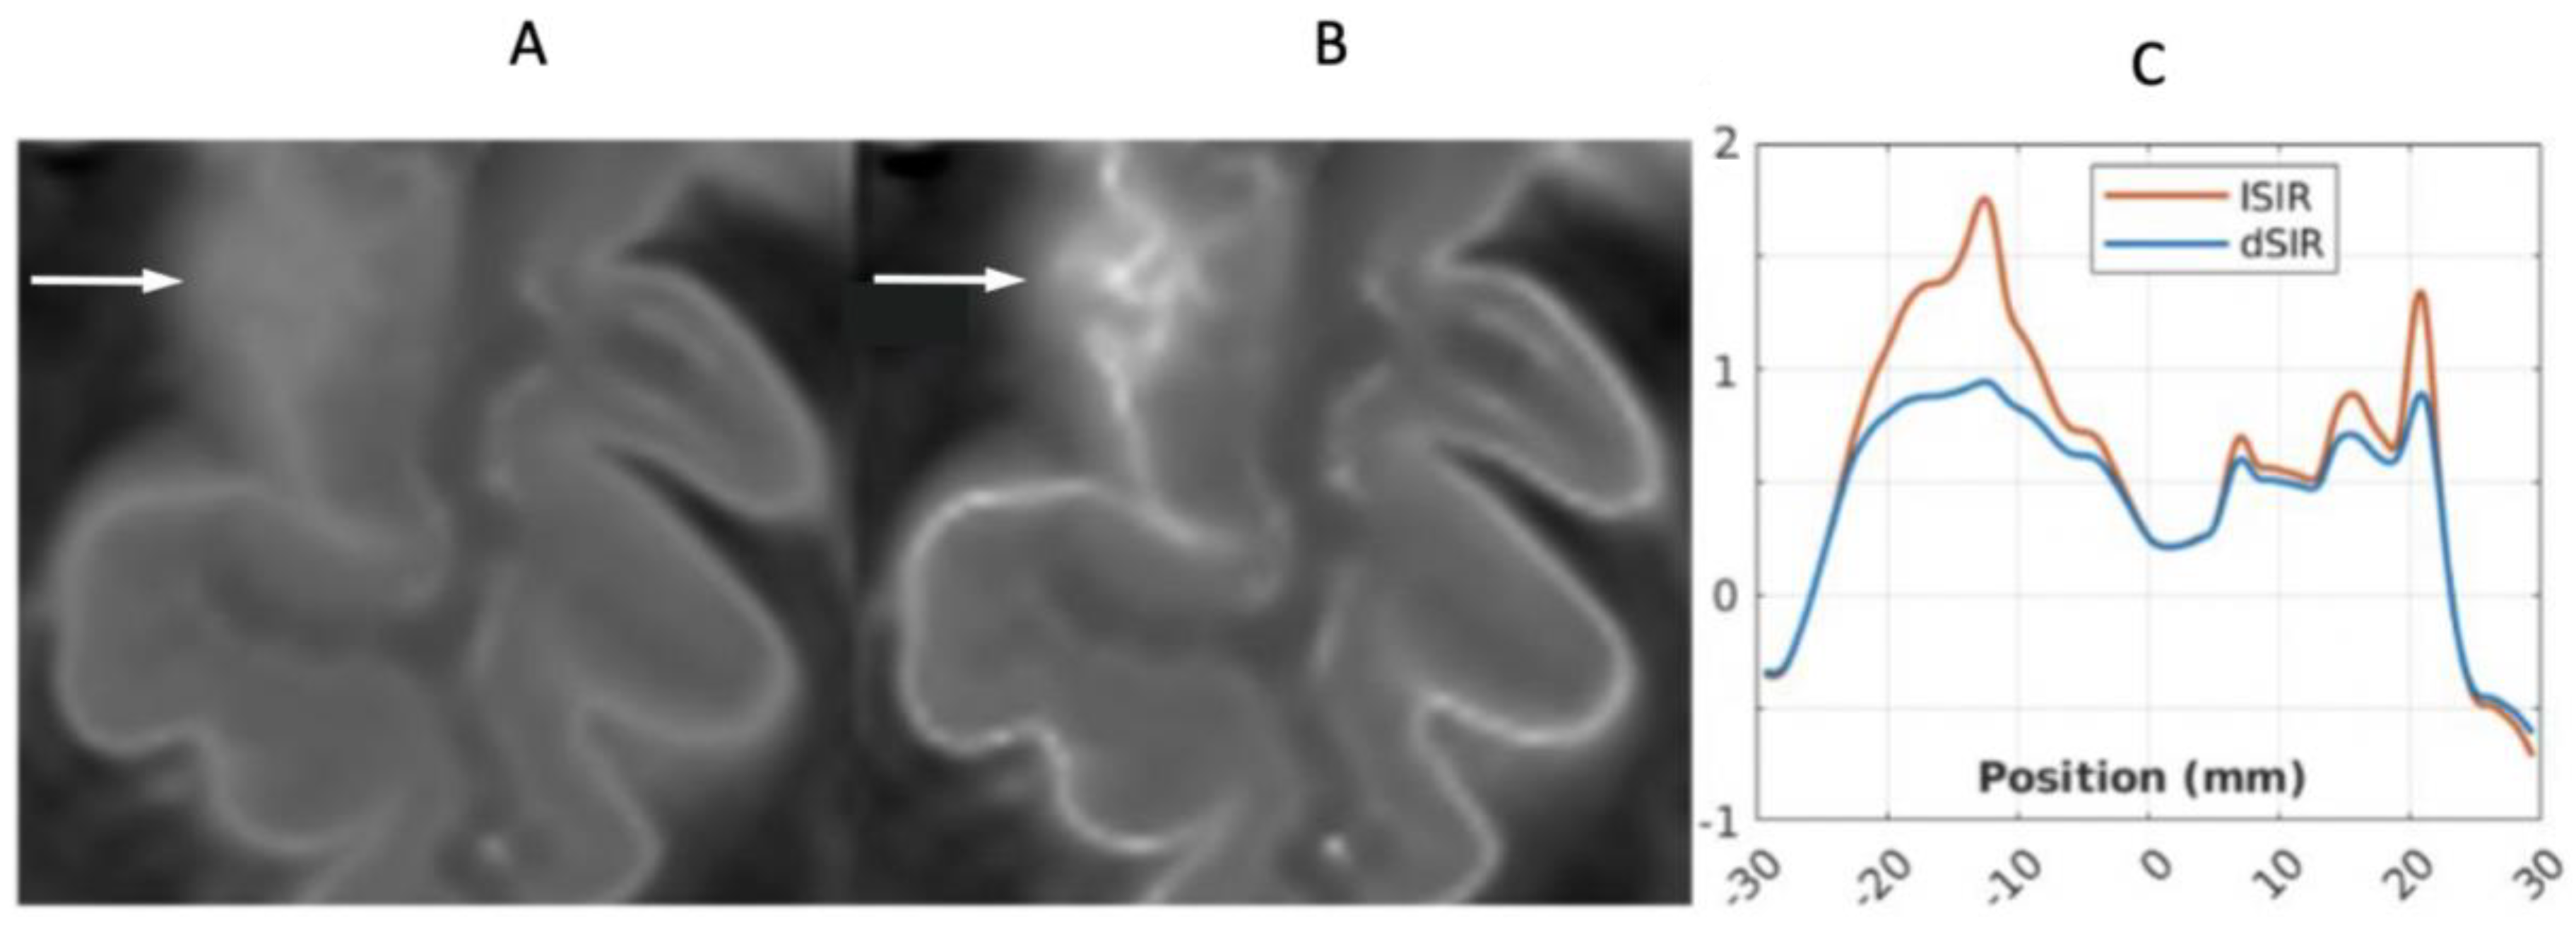

2.4. Log then Subtracted Inversion Recovery (lSIR) Sequences

2.5. Composite (c) Bipolar Filters (T1 as well as T2, T2*, and/or D*)

2.2. Contrast at Tissue Boundaries